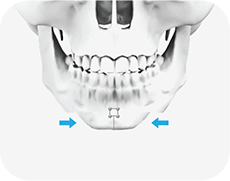

03

절제 된 양쪽의 뼈를 모아 가운데 고정